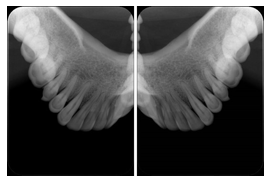

Intra-oral radiography typically involves acquisition of multiple images of various parts of the dentition. Many digital radiographic systems offer customized templates that are used for displaying the images in a study on the screen. These templates may also be referred to as mounts or view sets. The Structured Display Object represents a standard method of encoding and exchanging the layout and intended display of Structured Displays. A structured display object created in this manner could be stored with a study and exchanged with images to allow for complete reproduction of the original exam.

1. A patient visits a General Dentist where a Full Mouth Series Exam with 18 images is acquired. The dentist observes severe bone loss and refers the patient to a Periodontist. The 18 images from the Full Mouth Series along with a Structured Display are copied to a DICOM Interchange CD and sent with the patient to see the specialist. The Periodontist uses the CD to open the exam in his Dental Radiographic Software and consults via phone with the General Dentist. Both are able to observe the same exam showing the images on each user's display using the exact same layout.

Intra-oral Full Mouth Series Structured Display

Figure OO-1. Intra-oral Full Mouth Series Structured Display